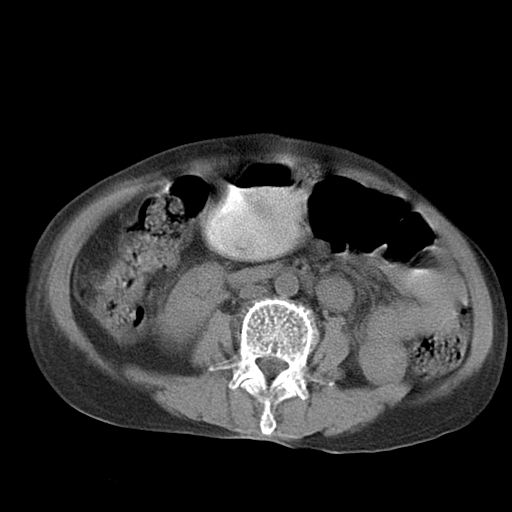

以下是引用dyqct在2006-12-7 21:08:00的发言:[br]考虑:1、肝内外胆管多发性结石伴肝左叶外侧段肝萎缩;[br] 2、右膈下多发脓肿;[br] 3、右侧少量胸腔积液、斜裂积液;[br] 4、左肾囊肿。

以下是引用jiazh在2006-12-7 20:37:00的发言:[br]肝脏周围半狐形低密度影,肝脏表面受压推移,考虑膈下脓肿可能性大;2、右侧胸腔积液

以下是引用拾荒者在2006-12-7 21:44:00的发言:[br]肝内外胆管多发结石,右膈下多发脓肿,右胸膜腔及叶间裂积液,左肾囊肿。[br] [br]